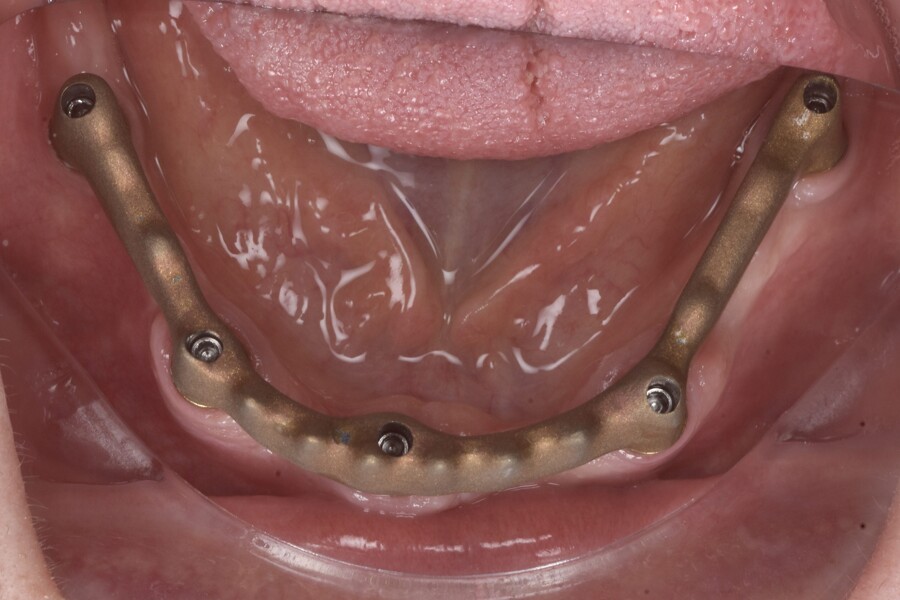

Fig. 5: Intra-op photograph after attachment of the osteosynthesis screws and implant placement.

At the surgery appointment, three osteosynthesis screws were placed to facilitate digital alignment of the preoperative and postoperative scans, and the remaining mandibular teeth were extracted, followed by full-thickness flap elevation. Minimal alveolar bone reduction was performed to improve ease of cleaning and to position the transitional line more apically. Five AnyRidge implants (MegaGen) were placed sub-crestally in native bone, avoiding the need for bone grafting (Fig. 4). Straight N-type multi-unit abutments (MegaGen) were connected and torqued to 35 N cm. The further prosthetic workflow was carried out entirely at the abutment level, avoiding implant–abutment disconnections and thereby simplifying the prosthetic procedures (Fig. 5). This approach is favourable for crestal bone stability.

Sufficient primary stability was achieved, enabling immediate loading, consistent with evidence-based recommendations.2–6 SmartFlag scan bodies (Apollo Implant Components) were attached, and the postoperative intra-oral scan was performed with both the scan bodies and the osteosynthesis screws in place (Figs. 6 & 7). The screws were removed after scanning.